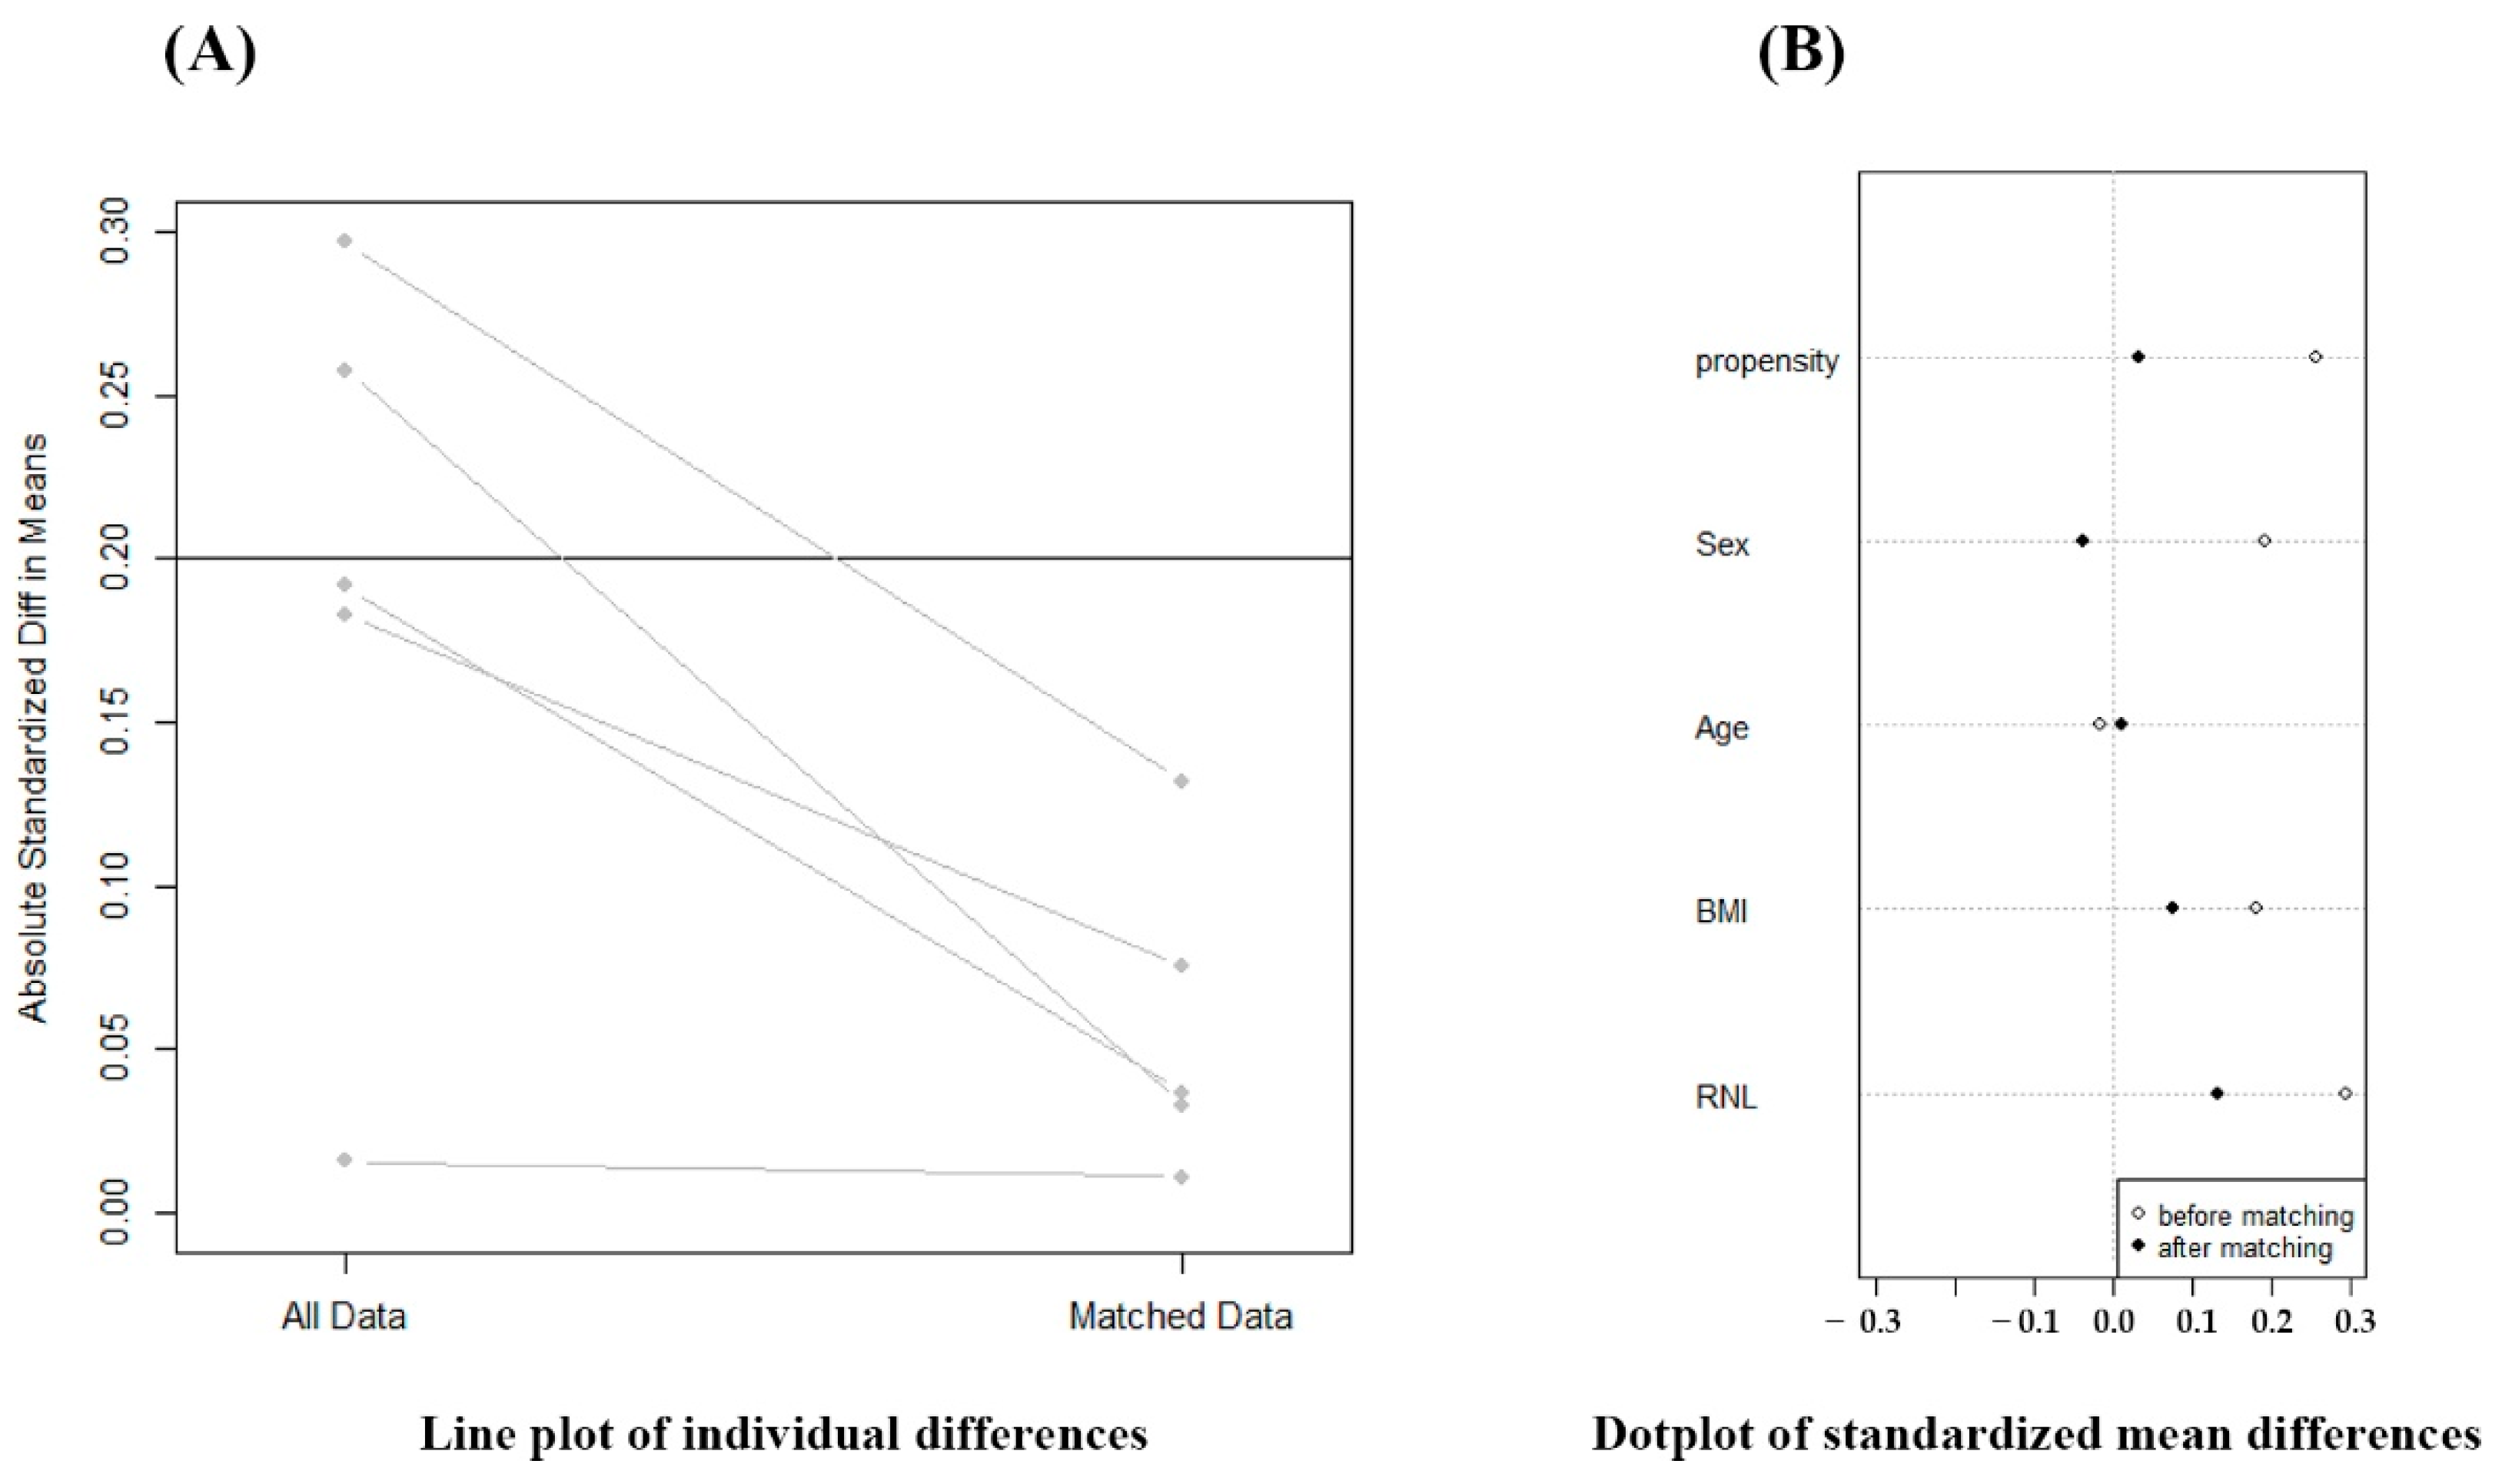

2.4. Statistical Analysis